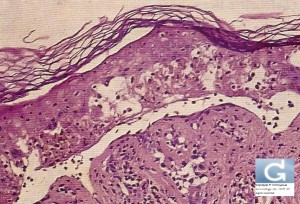

Toxic Epidermal Necrolysis (TEN, Lyell Syndrome): Histology of the skin shows necrotic keratinocytes with full-thickness epithelial necrosis and detachment